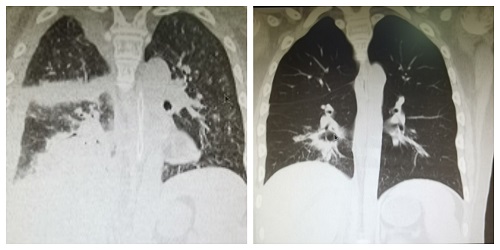

晓志患重型再生障碍性贫血,于当地医院行同胞全合造血干细胞移植后数日内出现反复高热、咳黄白黏痰,肺部CT显示大面积“白肺”伴大量胸腔积液,且病情进展迅速。呼吸衰竭的晓志已行呼吸机辅助呼吸,病情危急,立即邀请湘雅三医院李昕教授远程会诊,在她的建议下行肺泡灌洗并查找出病原菌——小孢根霉。经短期治疗调整病情仍持续恶化,并出现了血小板下降、大咯血,当地主管医生再次找到李昕教授,经湘雅三医院造血干细胞移植MDT团队远程会诊,考虑到患儿正处于“移植中”这一特殊时期,且小孢根霉感染需强有力的局部治疗,而当地医疗条件有限,建议尽快转诊。

图2:晓志入院时与出院前肺部CT对比

一个多月的治疗中,晓志经历了大量咳痰、窒息抢救、42℃高热、持续头痛、顽固性低钾、中耳炎等各种挑战,共进行了15次经纤支镜气管内两性霉素注射,2次移植MDT会诊及多次药物调整,所幸病情逐步得到控制。目前,晓志血象稳定、移植后嵌合良好、肺部感染平稳,已康复出院。